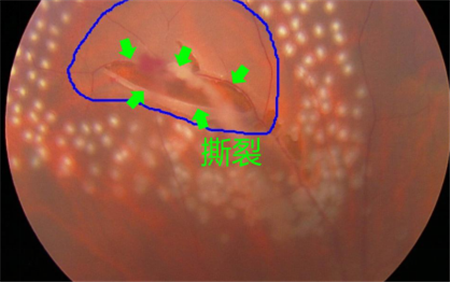

例如,對于視網(wǎng)膜撕裂引起的飛蚊癥,就需要對視網(wǎng)膜撕裂進(jìn)行治療,通過激光將裂孔周圍進(jìn)行燒焊凝固,以避免積水?dāng)U散造成嚴(yán)重的視網(wǎng)膜脫落;若飛蚊癥是由葡萄膜炎所致,就需要及時治療葡萄膜炎;對于糖尿眼導(dǎo)致的玻璃體出血,則需要通過激光治療以減少或避免增生血管的產(chǎn)生。